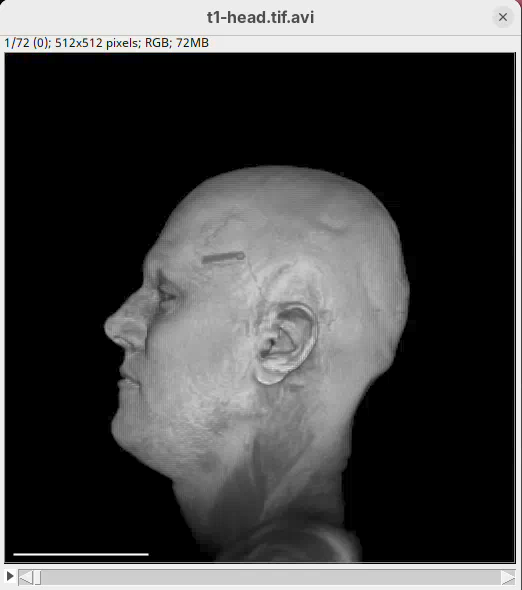

We will begin by visualizing an MRI dataset of a human head that is bundled in Fiji.

- Go to

File>Open Samples>T1 Head (16-bits).

- Increase the zoom to 200% for better visualization.

Orthogonal Views

Orthogonal Views is a tool that shows the optical sections through the orthogonal planes of XY: XZ and YZ. It is an easy and quick way to get a sense of the tridimensionality of your dataset. Whenever I’m opening a dataset for the first time I use Orthogonal Views. To activate it:

- Click on

Image>Stacks>Orthogonal Views(or pressCtrl+Shift+H). - The XZ and YZ panels will open next to your XY stack.

- The yellow lines are synchronized between the panels.

- Click around the different parts of the head to inspect the same position under different angles.

Orthogonal Views is a great way to start understanding your 3D data.